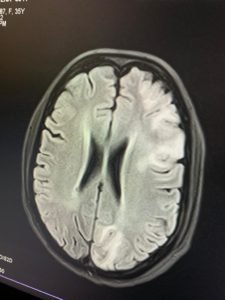

Case of the month: MELAS

A 35 year old female with infertility presented with seizure disorder. MRI brain showed flair hyperintensity in frontal ,parietal lobe and occipital frontal gyrus and olfactory gyrus . With enhancement in right caudate head and left occipital lobe Leptomeningeal enhancement in Parietal lobes .

Final diagnosis of MELAS ( Mitochondrial Encephalomyopathy, Lactic Acidosis, Strokelike Episodes )